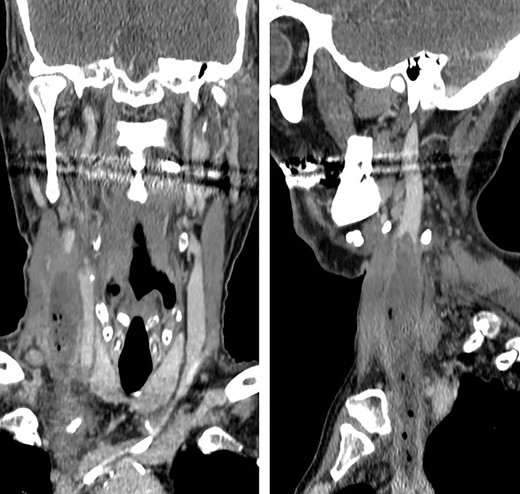

Axial CT view. Image shows a large diameter of right internal jugular vein and air bubbles inside the vessel.

Forty-eight hours later, the patient presented self-limited abdominal bleeding probably related to high dose of low molecular weight heparin (LMWH), which was treated conservatively. At the same time, hiccups appeared. It initially responded positively to haloperidol and chlorpromazine, but it progressed in frequency and intensity, becoming uncontrollable. A CT scan confirmed the absence of intraabdominal complication, and the patient was admitted to the intensive unit care to intensify hiccup treatment. During the next days, he started with fever peaks. Bacteraemia related to CVC was diagnosed, as well as inflammatory signs on the right jugular venous access. Due to the previous findings, a cervicothoracic CT was performed showing a thrombus and air bubbles into the right jugular vein. This conditioned a dilatation of an area of the vein intimately related to the phrenic nerve.

Different agents have been associated to hiccups etiology, which stimulate central or peripheral structures of the hiccups’ reflex arc [1, 2, 4]. Some of these agents, such as trauma, tumors, infections or metabolic diseases, produce persistent hiccups (lasting more of 48 hours) or even untreatable (2 or more months lasting) [1, 4]. In this patient, hiccup etiology was difficult to identify and resulted in a diagnostic challenge, because fever and cervical inflammatory signs appeared days after hiccups. When signs and symptoms came together, a cervical TC was performed, concluding that manipulation of CVC led to a septic thrombosis of internal jugular vein, its dilatation and, finally, the direct compressive stimulation of phrenic and vagus nerves (Figs. 1 and 2). Topaz et al described a case of uncontrollable hiccups after the insertion of a catheter into jugular internal vein because of the compression of phrenic nerve due to a hematoma [2, 3].